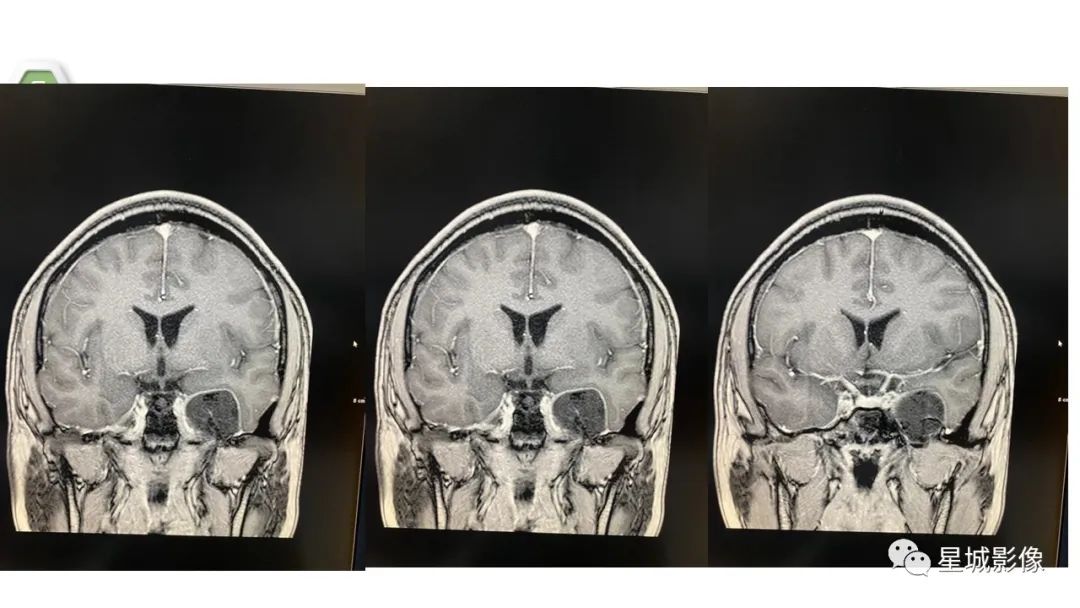

【病例】颅内成熟性囊性畸胎瘤1例MR影像表现-1

【病例】颅内成熟性囊性畸胎瘤1例MR影像表现-2

【病例】颅内成熟性囊性畸胎瘤1例MR影像表现-3